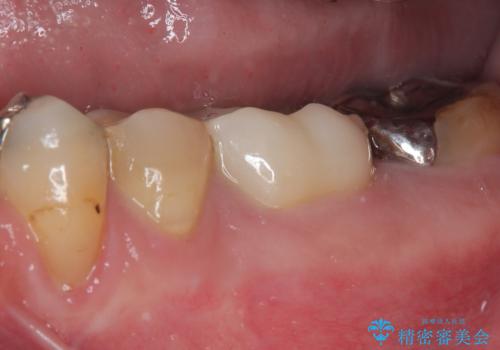

根管治療を実施した後に、フルジルコニアクラウンにて補綴することとしました。

症状のあった歯に対しても根管治療を行い、同様に補綴治療を行いました。